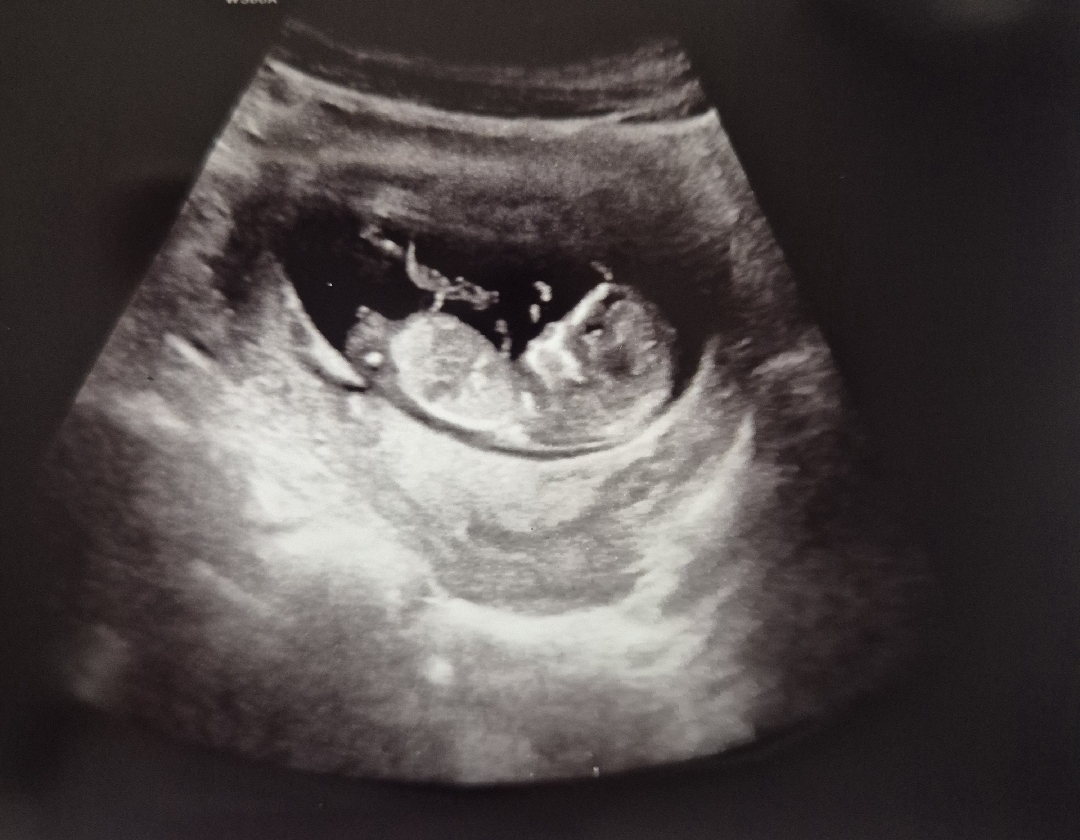

12주 2일차 초음파입니다!! 어떻게 보이시나요~~~??🥹